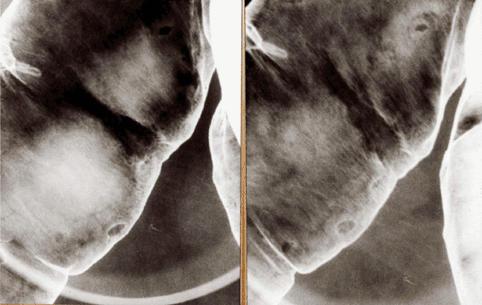

얕은 중앙함몰형의 변연부정"잠식상"으로부터 악성이라고 진단된 표면함몰형융기형(IIc+IIa형) 조기대장암)

[Image-ID:823]

악성 상피성종양/선암

대장/횡행

X-P

0형(표재형)/IIc형(IIc+IIa)

15~19

sm